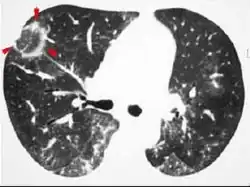

Infiltrat en verre dépoli

On appelle infiltrat en verre dépoli une image pathologique qu'on peut voir sur une radiographie pulmonaire ou en tomodensitométrie.

C'est un aspect de halo aux limites floues, focalisé ou diffus, sans systématisation.

L'arborescence vasculaire reste bien visible au sein de cet infiltrat.

Le grossissement de l’image révèle un aspect réticulé parsemé de très fins micronodules, ou un seul de ces aspects.

Cette image correspond à une hypertrophie inflammatoire du tissu interstitiel (parois alvéolaires et interstitium interlobulaire) qui devient radiologiquement individualisable.

Elle peut aussi correspondre au comblement partiel de la lumière de certaines alvéoles par des débris cellulaires ou par des membranes hyalines.